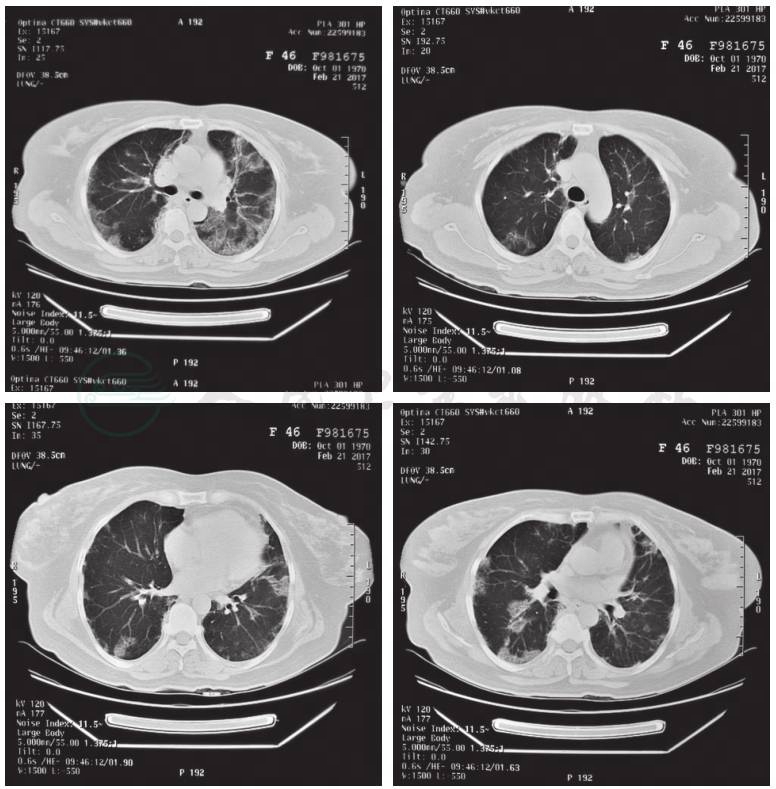

现病史:患者王某某,女性,46岁,某地方医院护理部主任。主因“发热伴喘憋5天,加重5天”急诊入解放军总医院呼吸与危重症医学科监护室。患者于2017年2月5日无明显诱因出现发热,咳嗽、咳少量黄色黏痰,自测体温37.8℃,无胸闷、胸痛,无恶心、呕吐等其他不适,自服“罗红霉素、氨溴索、板蓝根”后未见明显好转,下午体温最高达39℃,伴大汗、乏力、头痛。于当地医院就诊,给予头孢哌酮钠舒巴坦钠(舒普深)、左氧氟沙星、亚胺培南西司他丁(泰能)、氨溴索、甲泼尼龙等对症支持治疗,症状无好转,仍反复出现发热,咳嗽,咳中等量红色黏痰,伴喘憋、周身痛,体温最高达39℃,行胸部CT检查(2017年2月9日)示:双肺弥漫性炎性反应征象,左肺较右肺病变范围大(图1)。患者症状较前改变不明显,为进一步诊治,于2017年2月15日转至我院RICU住院治疗。

图1 胸部CT(2017-2-9):双肺弥漫性磨玻璃影和斑片影,左肺较右肺病变范围大,考虑炎性反应可能性大